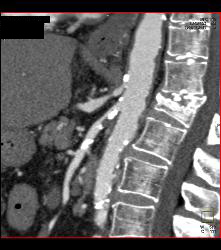

Timing for Bolus Tracking